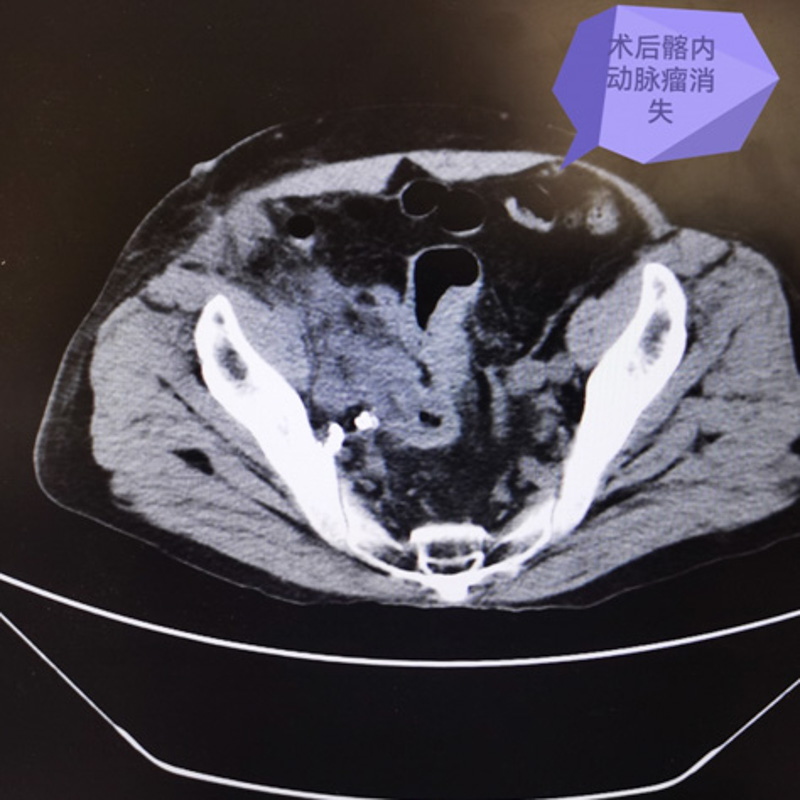

手術如期進行,血管外科主任霍鑫博士團隊首先利用腹腔鏡小心翼翼將髂動脈,髂靜脈,右輸尿管及粘連的腸道等組織與假性動脈瘤分離。結扎髂內動脈分支后,再在右側腹部切開8cm切口,取出巨大假性動脈瘤,手術完美收官。

術后賈老伯在醫護人員的照料下漸恢復良好,大小便困難的癥狀也消失了,他非常高興,對柳州市人民醫院醫護人員高超的技術贊嘆不已。一周后,患者便成功出院,回歸正常生活。